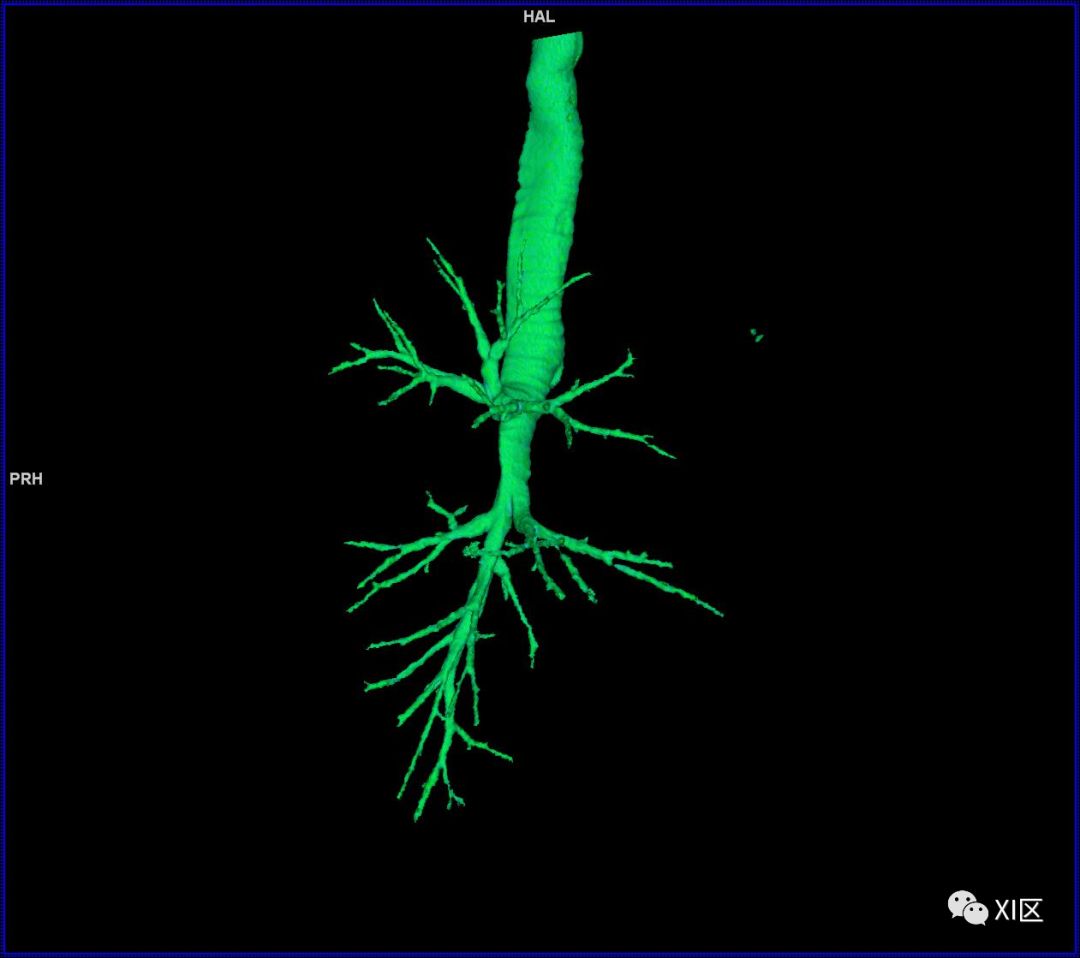

气管树的解剖

人的支气管(第1级)至肺泡约有24级分支。支气管经肺门入肺,分为叶支气管(第2级),右肺3支,左肺2支。叶支气管分为段支气管(第3~4级),左肺8支、右肺10支。段支气管就是肺的分段的依据。段支气管反复分支为小支气管(第5~10级),继而再分支为细支气管(第11~13级),细支气管又分支为终末细支气管(第14~16级)。从叶支气管至终末细支气管为肺内的导气部。终末细支气管以下的分支为肺的呼吸部,包括呼吸细支气管(第17~19级)、肺泡管(第20~22级)、肺泡囊(第23级)和肺泡(第24级)。 医学百科网 | YxBaike.Com

气管支气管形如树状,因此也称气管支气管树。 医学百科网 | YxBaike.Com

气管树 医学百科网 | YxBaike.Com

气管树与左右肺的关系